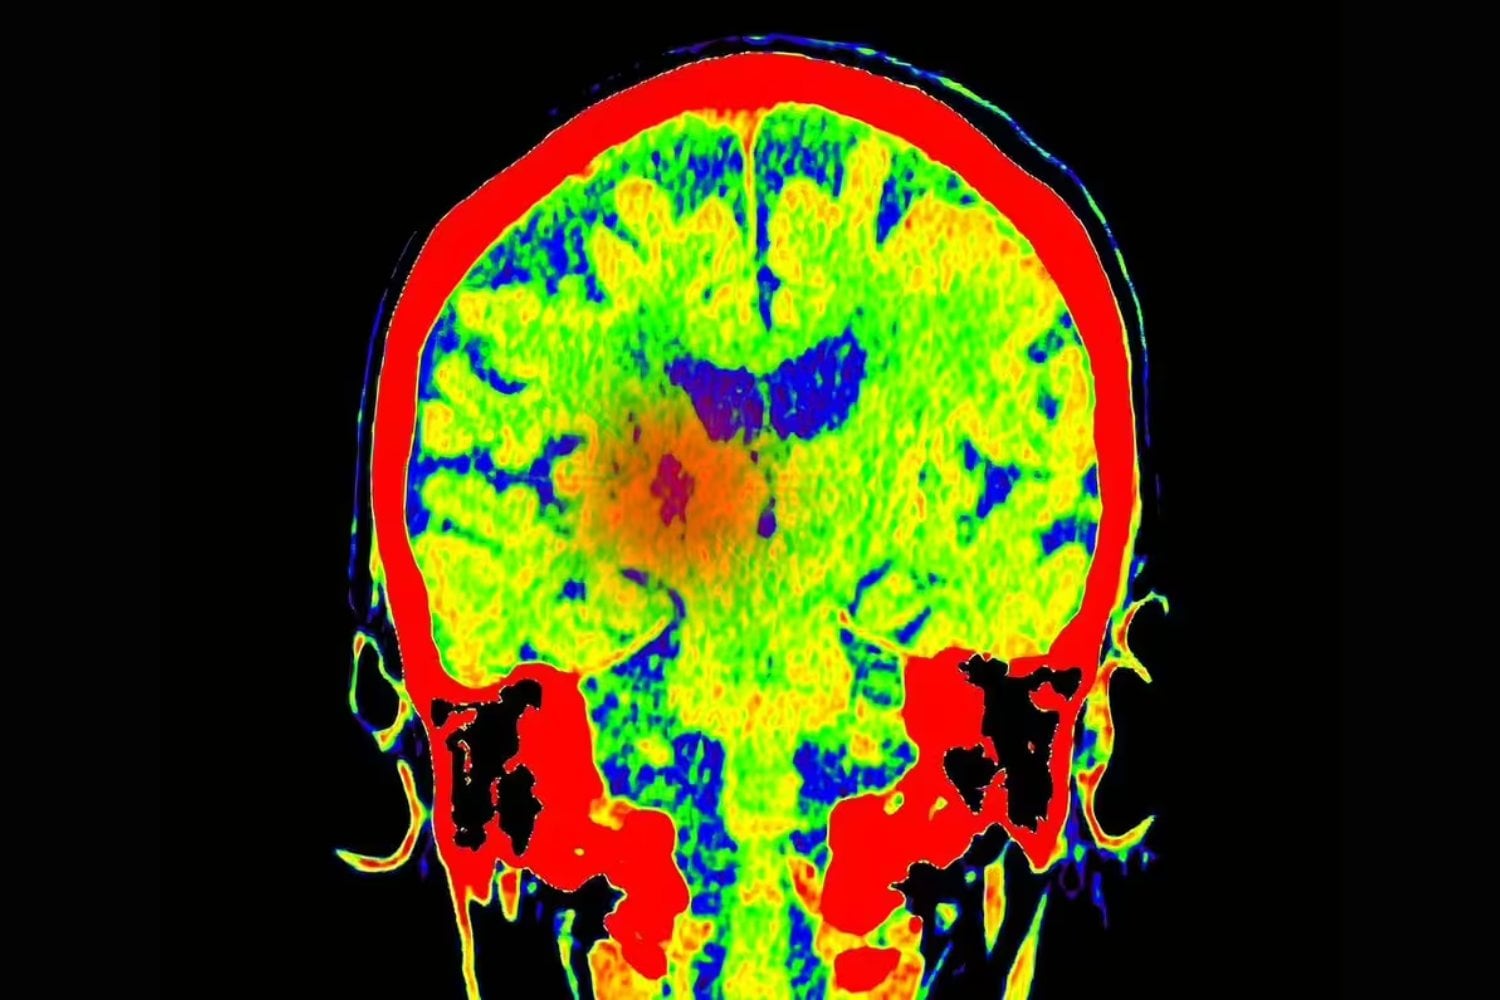

Un equipo de investigadores del Centro Médico de la Universidad de Georgetown ha identificado un papel clave de la proteína KCC2 en la velocidad con la que el cerebro establece asociaciones entre estímulos y recompensas. El trabajo, publicado en Nature Communications, aporta una pieza fundamental para entender cómo se forman tanto los hábitos cotidianos como las adicciones.

Según los investigadores, cuando la actividad de KCC2 disminuye en determinadas neuronas, el cerebro entra en un estado de “hiperaprendizaje”. Las neuronas dopaminérgicas (las encargadas de liberar dopamina, el neurotransmisor asociado a la motivación y la recompensa) se activan con más facilidad y de forma más coordinada. El resultado: el cerebro aprende asociaciones nuevas mucho más rápido de lo normal.

La dopamina no es la “hormona del placer” en sentido estricto, sino una señal de aprendizaje. Marca qué experiencias merecen ser recordadas y repetidas. El problema aparece cuando esa señal se amplifica en exceso. El estudio muestra que, con niveles bajos de KCC2, las neuronas no solo disparan más dopamina, sino que lo hacen de forma sincronizada. Esa coordinación genera picos de dopamina especialmente potentes, que asignan un valor desproporcionado a la experiencia asociada.

Los experimentos, realizados en ratones mediante análisis de tejido cerebral y pruebas de comportamiento, mostraron una relación clara: cuanto menor era la actividad de KCC2, más rápido y más fuerte era el aprendizaje asociado a recompensas. Este tipo de alteración también podría estar implicado en otros trastornos complejos, como la depresión o la esquizofrenia, donde los sistemas de recompensa y motivación funcionan de manera atípica.